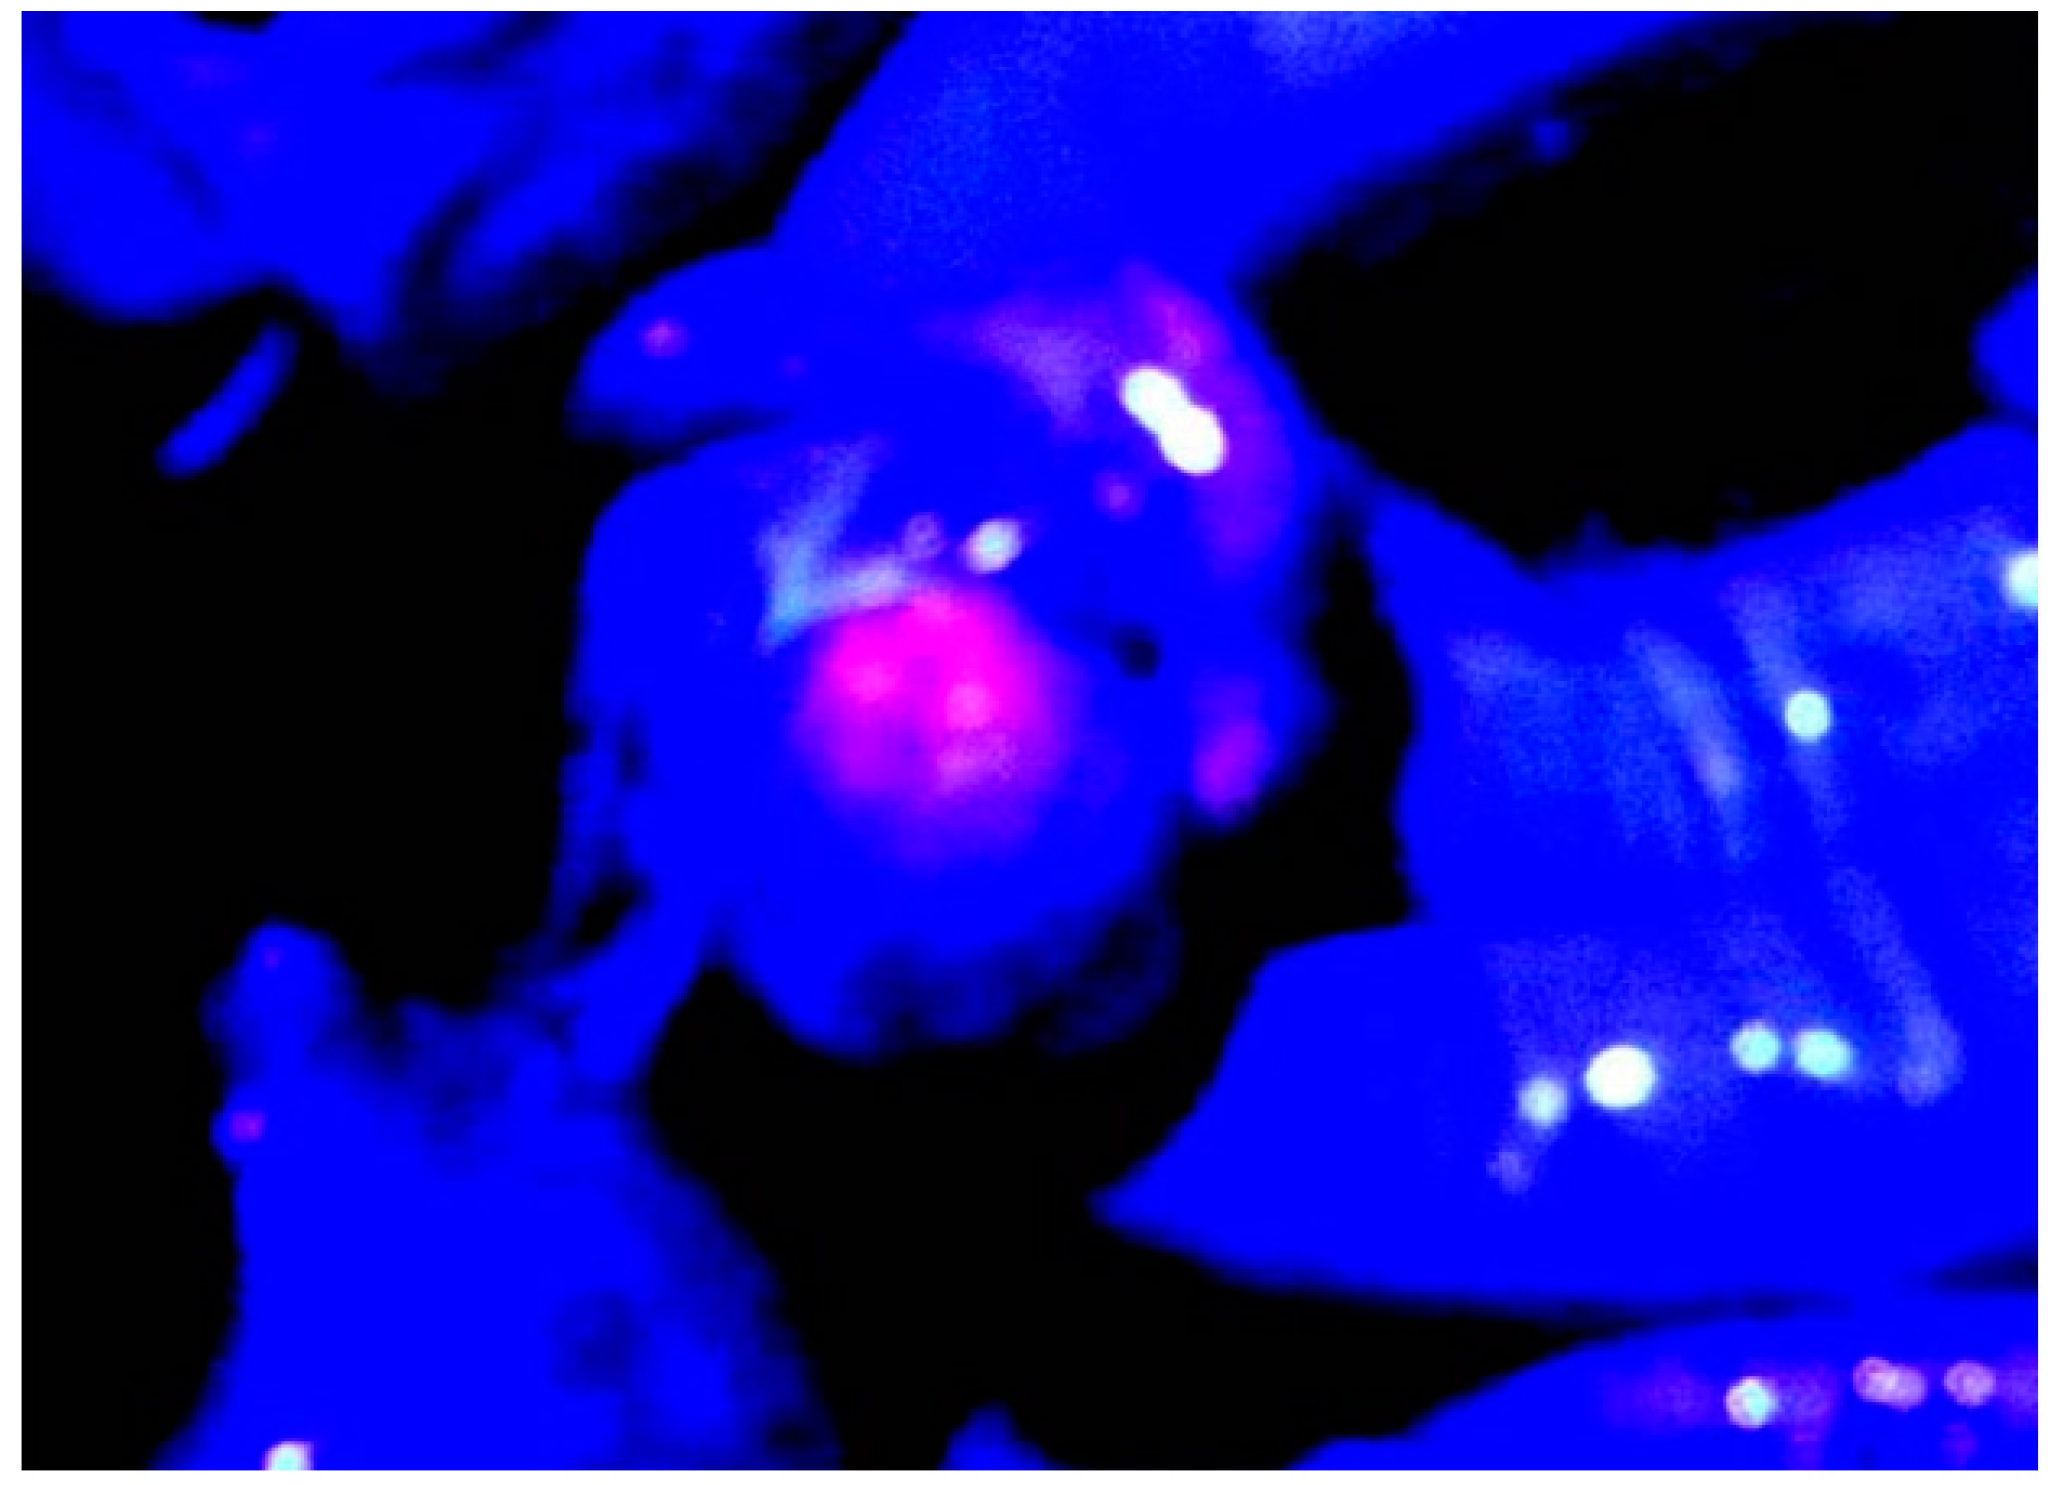

3.2. ALA PDD in Experimental PM

- Hino, H.; Murayama, Y.; Nakanishi, M.; Inoue, K.; Nakajima, M.; Otsuji, E. 5-aminolevulinic acid-mediated photodynamic therapy using light-emitting diodes of different wavelength in a mouse model of peritoneally disseminated gastric cancer. J. Surg. Res. 2013, 285, 119–126. [Google Scholar] [CrossRef]

- Canis, M.; Botchorishvili, R.; Berreni, N.; Manhes, H.; Wattiez, A.; Mage, G.; Pouly, J.L.; Bruhat, M.A. 5-amininolevulinic acid-induced (ALA) fluorescence for the laparoscopic diagnosis of peritoneal metastasis. An experimental study. Sur. Endoscopy. 2001, 15, 1184–1186. [Google Scholar] [CrossRef] [PubMed]

- Gahlen, J.; Pietschmann, M.; Prosst, R.L.; Herfarth, C. Systemic vs local administration of delta-aminolevulinic acid for laparoscopic fluorescence diagnosis of malignant intra-abdominal tumors-Experimental study. Surg. Endoscopy. 2001, 15, 196–199. [Google Scholar] [CrossRef]

- Hornung, R.; Major, A.L.; McHale, M.; Liaw, L.H.; Sabiniano, L.A.; Tromberg, B.J.; Berns, M.W.; Tadir, Y. In vivo detection of metastatic ovarian cancer by means of 5-aminolevulinic acid-Induced fluorescence in a rat model. J. Am. Assoc. Gynecol. Laparoscopist. 1998, 5, 141–148. [Google Scholar] [CrossRef]

- Lüdicke, F.; Gabrecht, T.; Lange, N.; Wagnières, G.; van Den Bergh, H.; Berclaz, L.; Major, A.L. Photodynamic diagnosis of ovarian cancer using hexaminolevulinate: A preclinical study. Br. J. Cancer. 2003, 88, 1780–1784. [Google Scholar] [CrossRef] [PubMed][Green Version]